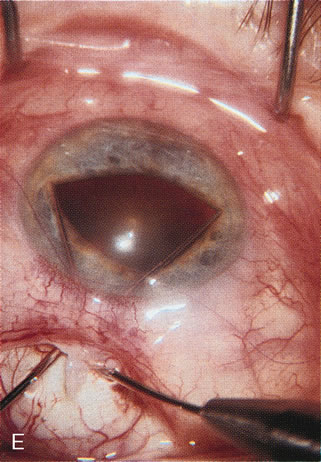

Fig. 7. Phacotrabeculectomy adjacent to a failed filter in cataractous eye. The ability to combine small-incision cataract extraction with trabeculectomy all through the same incision adjacent to the failed filter allows the surgeon to work in a familiar superior area. Avoiding incisions into the existing bleb decreases conjunctival buttonholes, hypotony, operating room time, and subconjunctival bleeding. A. Appearance of failed bleb with exposure of superior temporal quadrant gained with a corneal traction suture. B. Prepare a limbus-based conjunctival flap and a scleral flap. C. This bleb is at high risk to fail again justifying the need for MMC, 0.2 mg/cc applied on a pledget for 4 minutes. D. Insert the keratome and perform phacotrabeculectomy in the usual fashion.

The inflammation associated with lens extraction at any site usually causes complete failure of a marginal functioning bleb. In addition, pressure reduction by medical means is usually minimal in these recalcitrant cases, and combined surgery is indicated. In the past, these cases were approached with large-incision ECCE, clear corneal cataract incision, and bleb revision. Drawbacks included those mentioned earlier for large incision clear corneal cataract extraction, and bleb revision is often associated with conjunctival buttonholes, wound leaks, subconjunctival hematoma, destruction of friable sclera, and associated hypotony. With the advent of modern-day cataract surgery, a phacotrabeculectomy is often possible adjacent to the failed filter (Fig. 7). The ability to combine cataract extraction with implant and filtration surgery all through the same small incision has greatly improved outcomes for patients with marginal preoperative filters. There are several other viable options in this case. If the surgeon elects to remove the cataract through a temporal clear corneal incision, the bleb may be revised or a new adjacent filter fashioned. As mentioned earlier, revising a failed filter is technically challenging. If the surgeon believes it is not feasible to revise the filter or fashion a new one, a glaucoma drainage implant is a reasonable option combined with temporal lens extraction.172

CASE 6: ANTICIPATED LENS EXTRACTION POST FAILED TRABECULECTOMY WITH ADVANCED DISC DAMAGE AND IOP OUTSIDE TARGET PRESSURE RANGE